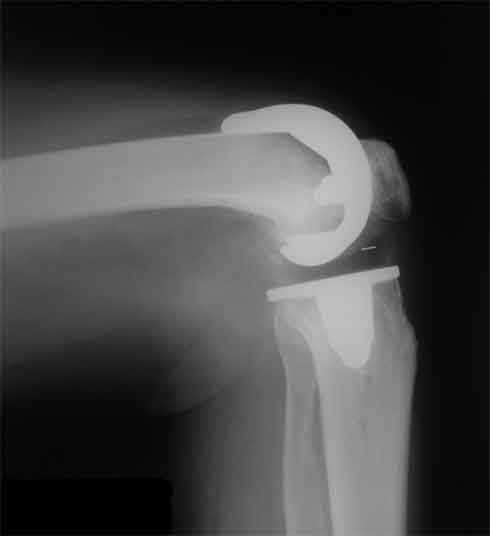

Оперирована пациентка 42 лет, избыточного веса. Выполнено б/ц протезированние коленного

сустава эндопротезом LCS. Послеоперационный период гладкий, в срок 2 мес. после операции

объем движений удовлетворительный, сгибание до острого угла, разгибание полное. В 3,5 мес.

во время падения подвернула ногу, после чего появилась. клиника медиолатеральной

нестабильности. В течении 3 недель фиксация в туторе. При повторном осмотре жалобы на

дискомфорт в коленном суставе, ╚ щелканье ╩ , неустойчивость в суставе. Вопросы/варианты

дальнейшей тактики лечения пациентки. 1) Существует ли способы восстановления внутренней

боковой связки на фоне протезированного коленного сустава и как добиться равномерного ее

натяжения при всех углах сгибания. 2) Ревизия с установкой более связанного протеза

(constrained) 3) Оставить как есть, ждать износа вкладыша, развития нестабильности

протеза, а затем идти на связанный протез. 4) Другие варианты.